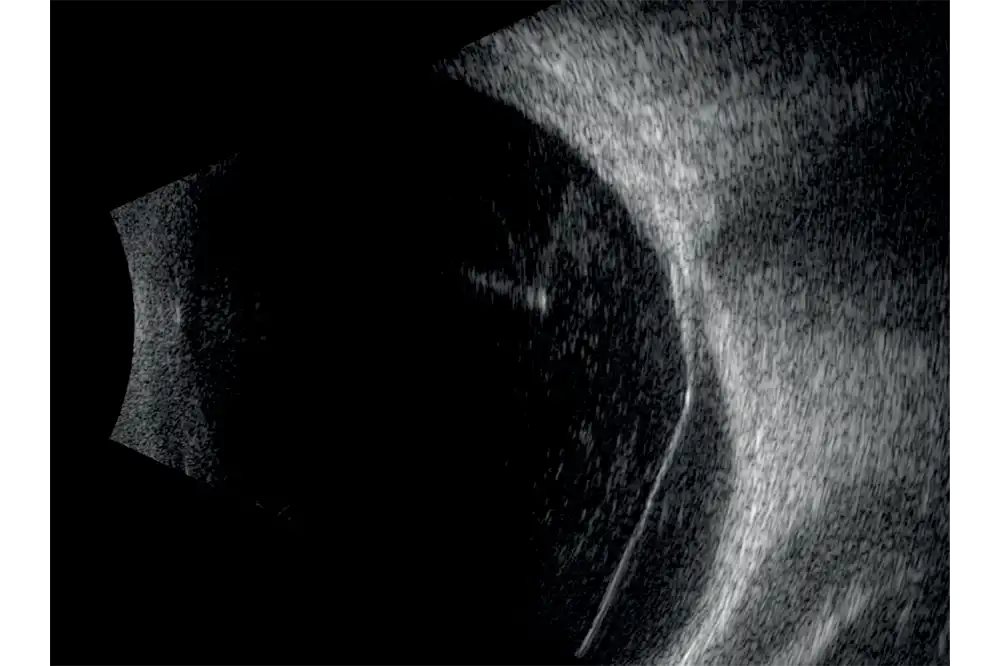

- Verhoogde scherptediepte waardoor het gehele oog zichtbaar is.

- Hoge resolutie die het mogelijk maakt om van het voorste gedeelte van het glasvocht tot aan de wand te zien.

- Nieuwe UBM technologie die verschillende beeldmodi mogelijk maakt.

- Exclusieve IMUv™-bewegingssensor maakt het mogelijk om de ultrasone bundel in real-time in het oogdiagram te lokaliseren.